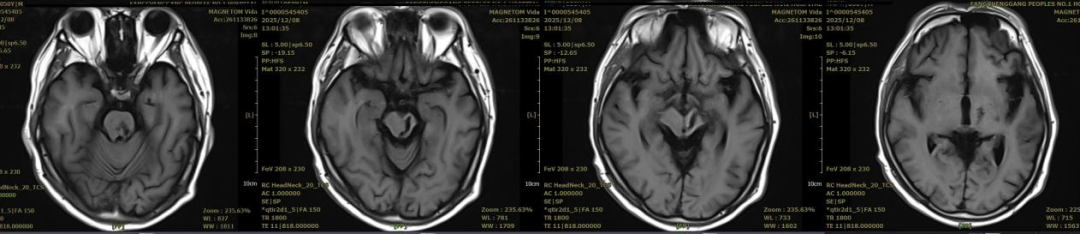

▲此次MR复查

患者恢复进程远超预期:在术后第5天便成功清醒,各项生命体征逐渐平稳,顺利转出重症监护室;经过科室规范的康复治疗与护理,患者逐步恢复生活能力,最终康复出院。